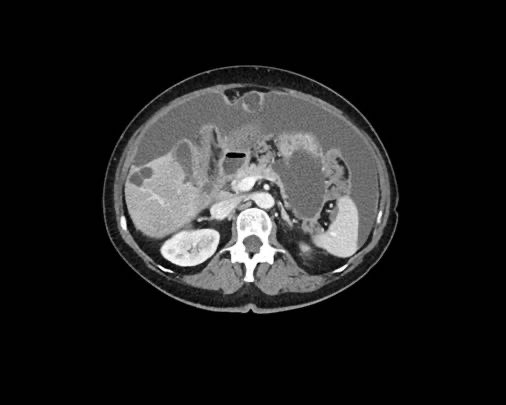

Ca lâm sàng 2

Cuộn qua các lát cắt.

Bạn có thể phát hiện tất cả các tổn thương cấy ghép phúc mạc không?